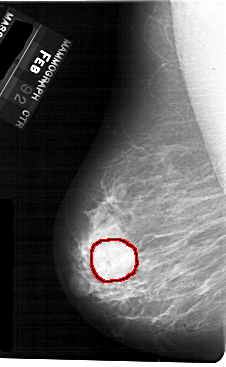

FILE: A_1710_1.LEFT_MLO.OVERLAY

TOTAL_ABNORMALITIES 1

ABNORMALITY 1

LESION_TYPE MASS SHAPE ROUND MARGINS OBSCURED

ASSESSMENT 3

SUBTLETY 5

PATHOLOGY BENIGN

TOTAL_OUTLINES 1

BOUNDARY